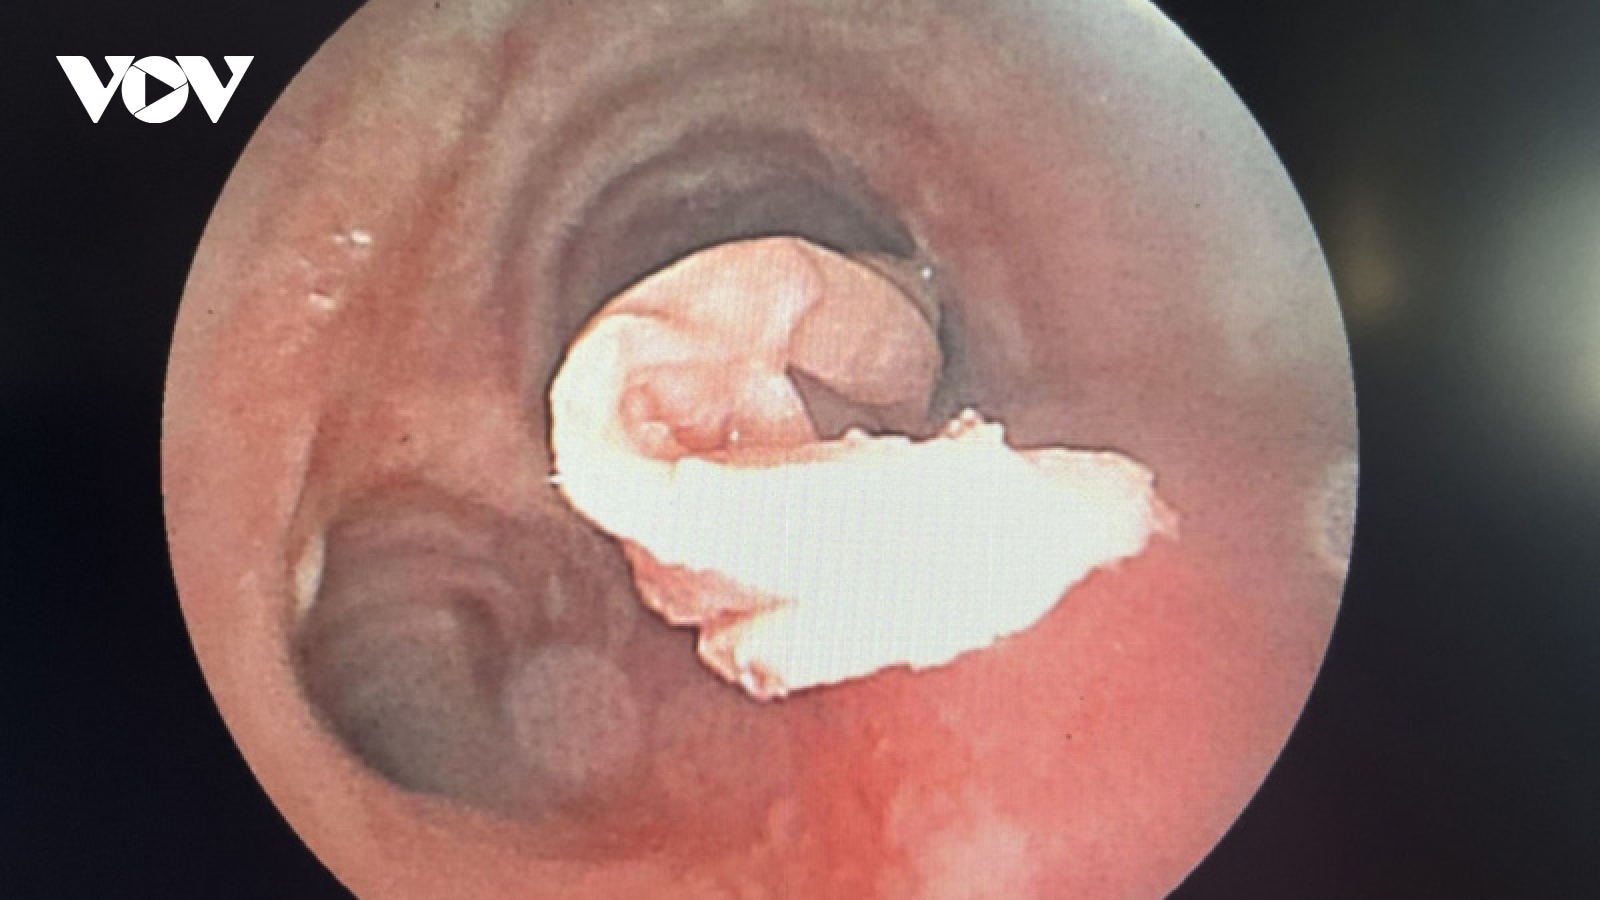

Dị vật khăn giấy trong phế quản bệnh nhân ung thư

VOV.VN - Ngày 21/7, Bệnh viện Đa khoa Trung ương Cần Thơ thông tin với sự phối hợp bác sĩ nhiều chuyên khoa đã nội soi thành công dị vật là đoạn khăn giấy (được se nhỏ) dài 15cm rơi trong phế quản ở bệnh nhân mở khí quản.